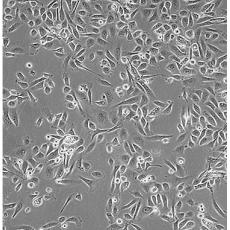

中文名稱(chēng) 人前列腺癌細(xì)胞

組織來(lái)源 前列腺癌;骨髓轉(zhuǎn)移;男性

生長(zhǎng)特性 adherent

形態(tài)特征 epithelial

細(xì)胞描述 PC-3源于一位62歲白人男性IV級(jí)前列腺腺癌患者的骨轉(zhuǎn)移灶;有低水平的酸性磷酸酶活性和5-α-睪酮還原酶活性。